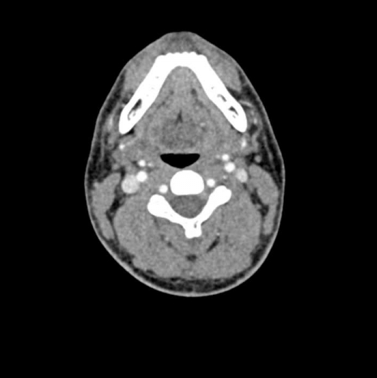

El maniquí de cabeza proporciona una simulación extremadamente realista de una angiografía por TC de cabeza y cuello (con contraste arterial) de un paciente con una malformación arteriovenosa en el lado derecho. El maniquí se entrega fiel a la escala original e incluye la columna cervical hasta la placa base de la quinta vértebra cervical.

Este fantasma se crea a partir de datos de pacientes reales y se fabrica con la última tecnología. Los huesos, vasos y tejidos blandos se muestran auténticamente con valores de TC realistas para todos los tejidos a un voltaje de tubo de 120 kVp en el TC. Si el maniquí se va a utilizar principalmente con otros voltajes de tubo (por ejemplo, 100 kVp), la calibración de los valores de CT se puede ajustar en consecuencia si es necesario. El fantasma proporciona contrastes de tejido realistas en las imágenes de rayos X. Los espacios aéreos se llenan con un material con aproximadamente -80 unidades Hounsfield.